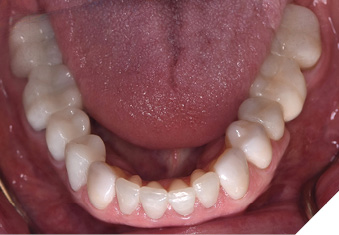

A 65-year-old woman comes to the office with the chief complaint of worn-down teeth, missing teeth, tooth sensitivity, especially on maxillary teeth and TMJ pain. Her past medical history was reviewed and was significant for asthma, insomnia, hypercholesterolemia, hypothyroidism, and anxiety disorder. She denied any sleep disturbances. Her medications included salbutamol, ezetimibe, quetiapine, and levothyroxine. She referred to being allergic to dust and shellfish and sensitive to propofol. She had a right mastectomy in 2014 due to breast cancer. No chemotherapy or radiation was done. Her diet was considered normal, and she denied any consumption of acidic drinks and denied any history of regurgitation. She denied any parafunctional habits during the day. She was using a maxillary transitional partial denture since she had lost some of her teeth due to fracture and caries. No other problems were evidenced. Intraoral exam showed moderate attrition lesions of posterior teeth, porcelain fused to metal crowns on teeth 46 and 47 had the porcelain portion worn down, exposing the metal substructure. Missing teeth included teeth 14,15,16,18,24,28, 36,38,48. Palatal surfaces of maxillary anterior teeth also appeared worn down. An abfraction lesion was found on tooth 23. No carious lesions were found in any of her teeth. Composite restorations on mandibular anterior teeth were chipped or were missing (Figs. 6-11) She also presented with limited mouth opening: 35 mm interincisal distance at maximum opening. There was bilateral pain on palpation of preauricular areas. Her pain was the worst early in the morning which suggested night parafunction. No crepitus, or joint clicking were found.

Fig. 6

Fig. 7

Fig. 8

Fig. 9

Fig. 10

Fig. 11

Articulated diagnostic casts showed very limited to no overjet and 90% of overbite. The wear pattern on the palatal aspect of her maxillary teeth appeared to be secondary to her tight occlusion since mandibular anterior teeth were in close contact with these surfaces with no “room” for protrusive movements. The diagnosis for this patient was: partial edentulism, failing existing restorations and attrition and abfraction secondary to parafunction. We discussed different options, including orthodontics in order to increase her overjet so we could have prosthetic space to restore her worn down teeth. We also discussed tooth replacement options. After a second consultation appointment which she attended with her husband, she decided that she did not want to replace her teeth with removable prosthetics. She also declined referral to an orthodontist. After discussion of multiple options of treatment to address all her chief complaints, her treatment consisted of a full mouth reconstruction with full coverage restorations in Zirconia for teeth 11-13,17,22-23,25-27,32-42, 44-47 and partial coverage restorations with lithium disilicate restoration for teeth 33,34 and 43. Replacement of teeth was achieved with a fixed partial denture to replace tooth 36 and a 3-unit implant supported bridge to replace teeth 24-26. In terms of occlusion, we created a more favorable occlusion with a proper anterior guidance, canine disclusion with more freedom for protrusive movements, which hopefully would decrease the parafunction, and alleviate some of her muscle pain. Before completing the case, the patient spent several weeks with provisional restorations which reflected the increase in vertical dimension of occlusion and the new occlusal scheme. During this trial phase, we assessed comfort, esthetics, function, decrease in pain and speech (Figs. 12-17).